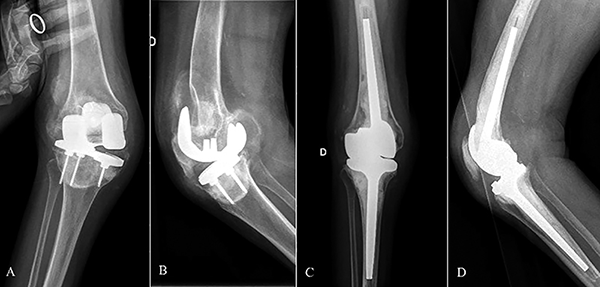

Figura 1: Caso 17. A y B) Paciente de setenta y ocho años con genu valgo severo. C y D) Artroplastia total de rodilla con prótesis abisagrada Endo-Model.